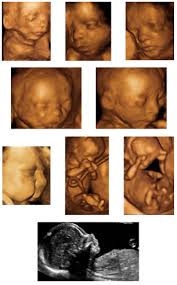

How Much Is A 3d Ultrasound Cost 2021 At En Mdg Sdg3d Undp Org

How Much Is A 3d Ultrasound Cost 2021 At En Mdg Sdg3d Undp Org from i.pinimg.com